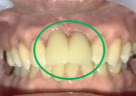

右上2本(第1第2小臼歯)の虫歯を治したい。

レントゲンで詳しく診てみると、虫歯が歯根のほうまで進行し、保存することができないことがわかり、抜歯しました。抜歯後、骨が大きく欠損していましたので、骨造成を行いインプラントを2本埋入しました。

抜歯後の欠損したところを補う方法には、部分入れ歯、ブリッジ、インプラントがあることを説明したところ、自分の歯と同じような感覚で嚙むことができるインプラントを選択されました。この方は、2016年に右下にインプラント治療をし、インプラントの良さを十分に理解しておられましたので、今回も2本歯を失ったところにインプラント治療を希望されました。今回もX-Guideを使った埋入で、安心安全に行うことできました。